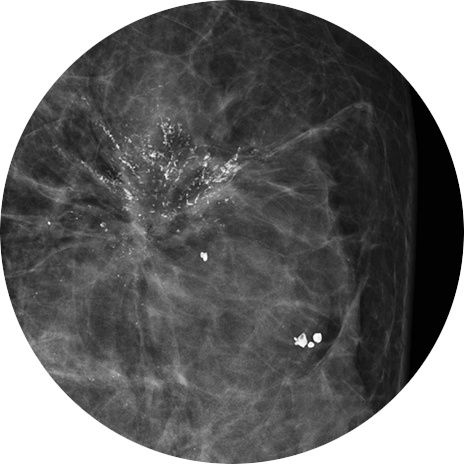

유방촬영술에서 악성이 의심되는 미세석회화가 발견되면, 석회화의 분포와 모양을 보다 정확히 평가하기 위해 확대촬영을 시행합니다.

미세석회화는 다양한 원인에 의해 발생할 수 있으며, 유방암을 포함하여

과거의 유방 염증, 외상, 유선 분비물의 정체 등과 관련될 수 있습니다.

확대촬영에서 미세석회화 모양이 양성인 경우에는 6개월 추적검사를 시행합니다 확대촬영으로 유방암이 의심되는 미세석회화가 있으면, 입체정위 유방생검을 통해 미세석회화 조직을 얻습니다. 얻은 미세석회화 조직을 병리과에서 분석하여 유방암을 진단하게 됩니다.